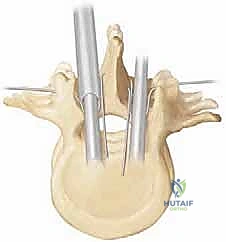

The osteology of the neuromuscular spine presents significant fixation challenges. Disuse osteopenia, combined with the effects of anti-epileptic medications and poor nutritional status, renders the vertebral bodies and posterior elements structurally compromised. The unit rod technique elegantly circumvents the limitations of poor cancellous bone density (which plagues pedicle screw fixation in this population) by utilizing the cortical bone of the laminae. The sublaminar space, bounded anteriorly by the dura mater and posteriorly by the ligamentum flavum and lamina, is the critical anatomic zone for this procedure. The surgeon must navigate this space with extreme precision, utilizing doubled 16-gauge or 18-gauge wires. The epidural venous plexus is often engorged, particularly in the prone position, and careless wire passage can result in catastrophic epidural hemorrhage or direct contusion to the spinal cord.

3. Sublaminar Wire Passage

This is the most perilous phase of the procedure. The ligamentum flavum is meticulously excised at the midline using Kerrison rongeurs to expose the epidural space. Doubled 16-gauge or 18-gauge stainless steel wires, pre-bent into a smooth, semi-circular loop, are carefully passed under each lamina.

The technique requires a delicate "flossing" motion. The tip of the wire must be kept in direct contact with the undersurface of the lamina at all times to avoid plunging into the spinal cord.

Once the loop emerges from the cephalad edge of the lamina, it is grasped with a nerve hook and pulled through. The wires are then sharply bent over the posterior elements to prevent them from slipping back into the canal and compressing the cord.